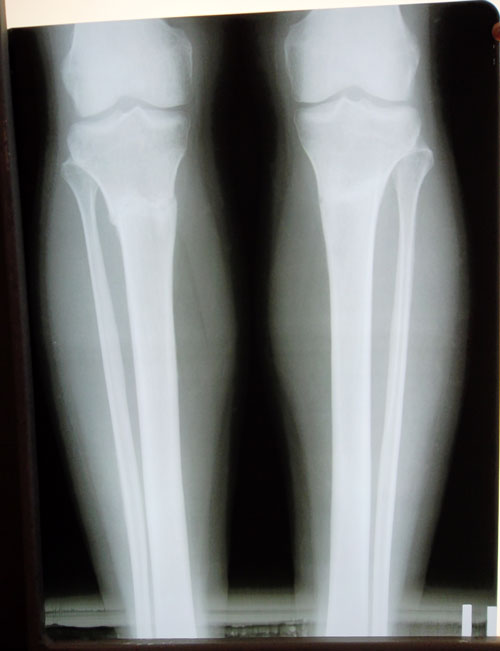

Дата операции 14.11.2013г.

Дата снятия аппаратов 24.03.2014г.

Срок лечения 130 дней.